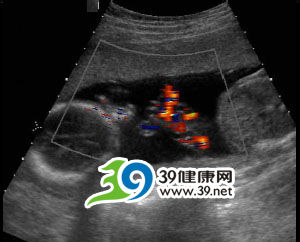

脐带危险六:单脐动脉

正常的脐带中有两条脐动脉,一条脐静脉。如果胚胎发育出现异常,脐带中只有一条脐动脉就称为单脐动脉。显而易见,单脐动脉时胎儿获得的血流量比正常少,所以导致胎儿早产、生长迟缓、胎儿宫内缺氧的机会增高。

诊断及处理

现在大多通过产前B超检查就可确诊。目前对于这种异常没有治疗方法,应密切注意胎儿的状况,如果胎儿一直没有缺血、缺氧出现,就可以继续怀孕,直至分娩。